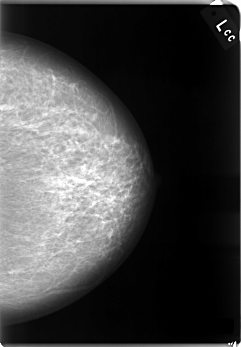

C_0003_1.LEFT_CC

LEFT_CC LINES 5896 PIXELS_PER_LINE 4088 BITS_PER_PIXEL 12 RESOLUTION 50 NON_OVERLAY

LEFT_MLO LINES 5832 PIXELS_PER_LINE 4104 BITS_PER_PIXEL 12 RESOLUTION 50 NON_OVERLAY